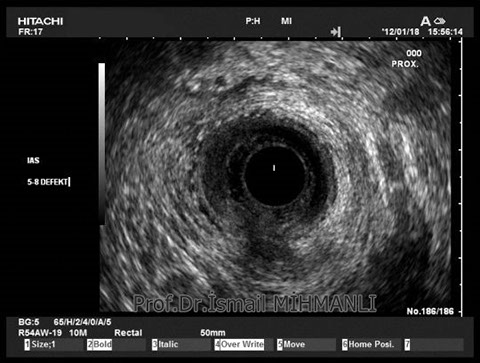

PERİANAL FİSTÜLLER Perianal fistül ve abselerin intersfinkterik anal bez iltihabından kaynaklandığı düşünülmektedir. Crohn hastalarında perianal enflamatuvar hastalık sıktır. İntersfinkterik mesafedeki enfeksiyon yukarıda rektuma, aşağıda cilde, yanlarda dış sfinkteri geçerek iskiyoanal mesafeye uzanabilir. Primer fistülün sfinkterler ile ilişkisini ve abse veya sekonder dal varlığını ameliyat öncesi bilmek, tedavi planı açısından önemlidir. İskiyoanal ve iskiyorektal mesafe tutulmamışsa hastalık daha kolay tedavi edilir. Bu mesafelerde abse veya sekonder bir dal varsa fistül komplekstir ve tedavisi kompleks olmayan fistüle göre değişik olabilir. Bundan dolayı, primer fistül traktı anatomik yerleşimine göre geleneksel olarak sınıflandırılır. Bu sınıflama dörde ayrılır: 1- İntersfinkterik (iç ve dış sfinkter arasında), 2- Transsfinkterik (dış sfinkteri geçerek iskiyoanal veya iskiyorektal mesafeye ulaşmış), 3- Suprasfinkterik (intersfinkterik plandan yukarı doğru uzanan traktüs puborektal kasın Genel Gaz ve Dışkı Kaçırma (Anal İnkontinans) Perianal Fistüller Rektal Tümörler Anal Tümörler Kabızlık Yazılarımız üstündeki bir seviyeden yana kıvrılarak tekrar aşağıya iskiyoanal mesafeye uzanmış), 4- Ekstrasfinkterik (sfinkterlerin dış tarafında rektumdan direkt olarak perianal cilde uzanan traktüs). Endoanal ultrason ile hem primer fistül, hem de varsa sekonder dal ve abse doğru bir şekilde tanınır. Endoanal ultrason ile fistülün anal kanala açılan kısmını (iç uç) görmek kolaydır. Bu hastalarda sfinkter defektlerine de rastlanmaktadır. Sfinkter defekti endoanal ultrason ile kolaylıkla tespit edilir. (bkz. anal inkontinans) Perianal fistül şikayeti olan hastaların az kısmında endoanal ultrason ile bir şey görülemez ise endoanal ultrason probuna ek olarak lineer prob ile anal kanal çevresine bakmak yararlıdır. Çünkü anal kanal bileşenlerinin uzağındaki bir enflamasyon ancak bu problar ile tanınabilir.